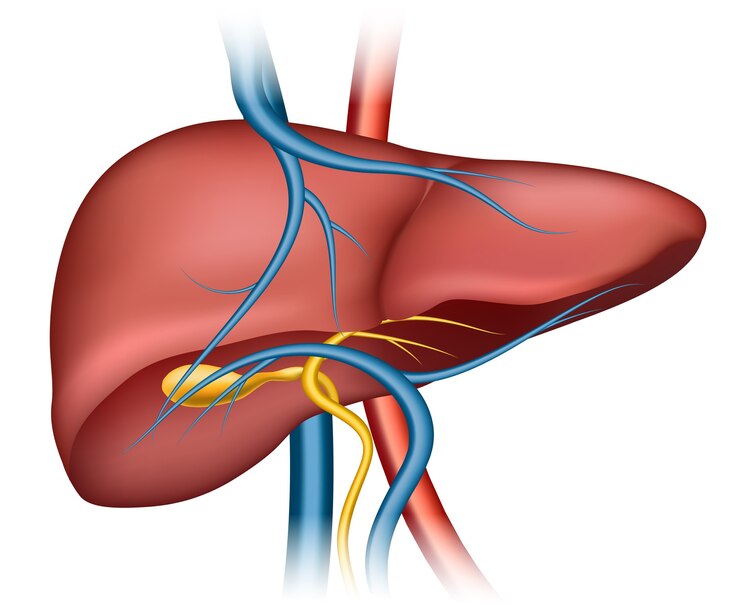

Liver Cleansing (Flushing gallstones from gallbladder)